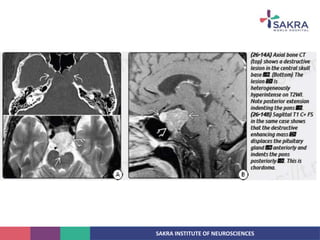

• NCCT:

• Relatively well circumscribed, moderately hyperdense midline or paramedian clival

mass with permative lytic bony changes.

• Intratumoral calcification generally represent sequestration from destroyed bone.